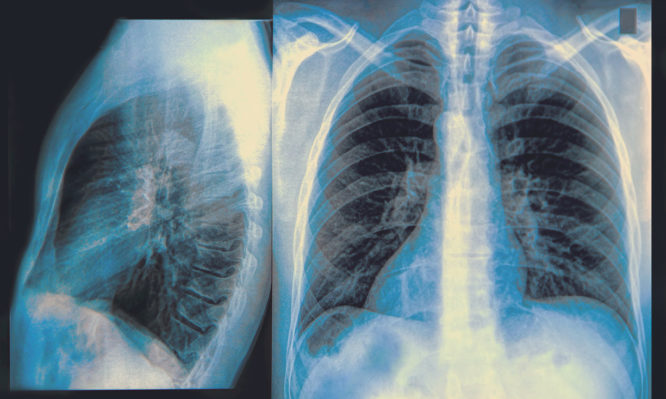

Πνευμονική υπέρταση: Ποια συμπτώματα πρέπει να οδηγήσουν τους ασθενείς στον γιατρό

Εάν αφεθεί χωρίς θεραπεία, η πνευμονική υπέρταση μπορεί να οδηγήσει σε καρδιακή ανεπάρκεια και θάνατο.